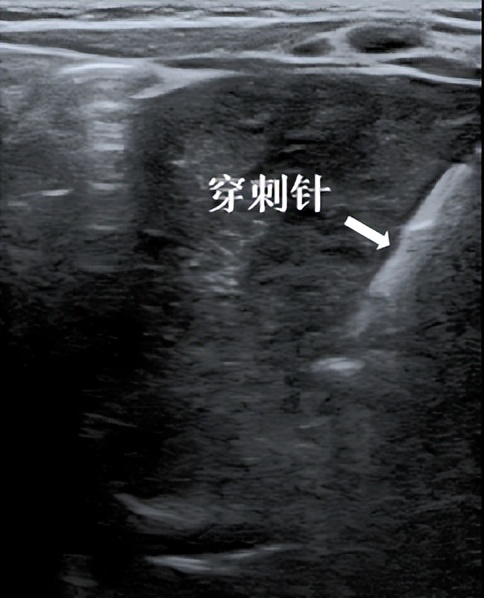

为取得病理结果、明确诊断,小儿血液科与超声科、麻醉科医师会诊沟通,全面评估小亮亮的情况,并在取得家属同意后,在全麻下进行了 超声引导下肝脏肿瘤穿刺活检术 。

手术过程顺利,小亮亮生命体征平稳,术后腹壁仅见微小穿刺针眼,没有明显不适。穿刺组织常规病理结合免疫组化,最终诊断为肝母细胞瘤,为下一步诊治提供了有力证据。

超声引导下穿刺活检 是在超声实时引导下,将穿刺针送入病变内部,从病灶内取一些组织进行病理检查,以明确病变的性质。整个穿刺过程约十几分钟,一般只需局麻,婴幼儿等无法配合者需全麻。整个过程可清晰显示穿刺针的路径和位置,精准安全。

超声引导下穿刺活检可视、精准、快速、无辐射,能够避开重要的血管、组织和器官, 创伤小、伤口恢复快、能够有效获取标本进行常规病理及免疫组化、基因检查,为临床诊断及治疗提供重要依据,有利于医生制定个体化的诊疗方案。